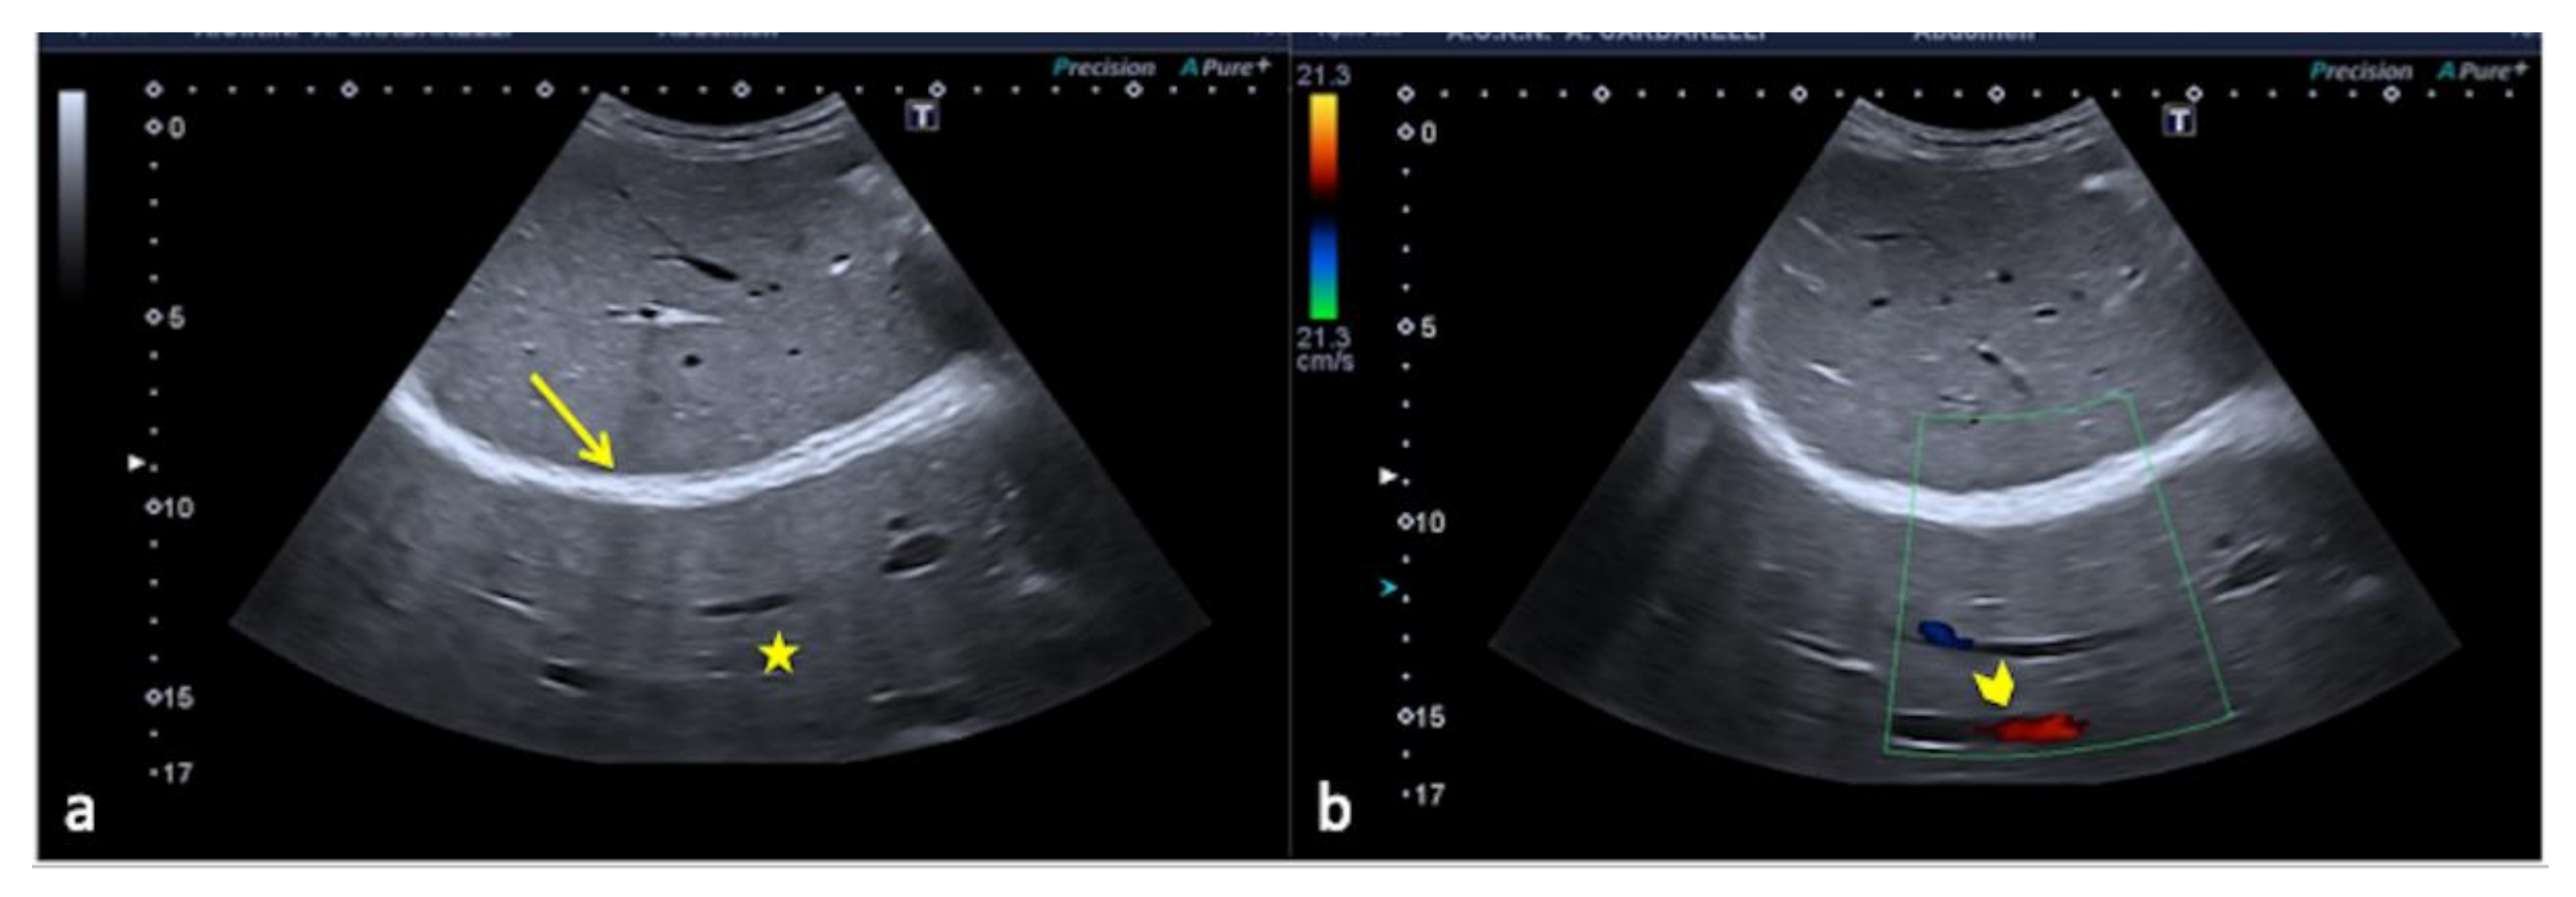

3.1.2. The Mirror-Imaging Effect